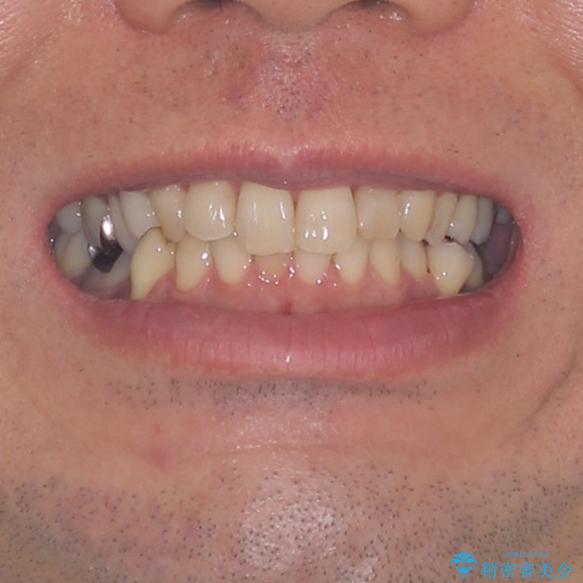

外側に飛び出した歯 インビザラインによる矯正治療

- 外に飛び出した側方の歯と、前歯のデコボコを気にして来院された患者様です。

IPR(歯と歯の間を削る)によってデコボコが解消するように設計し、インビザラインにより治療を行うこととしました。